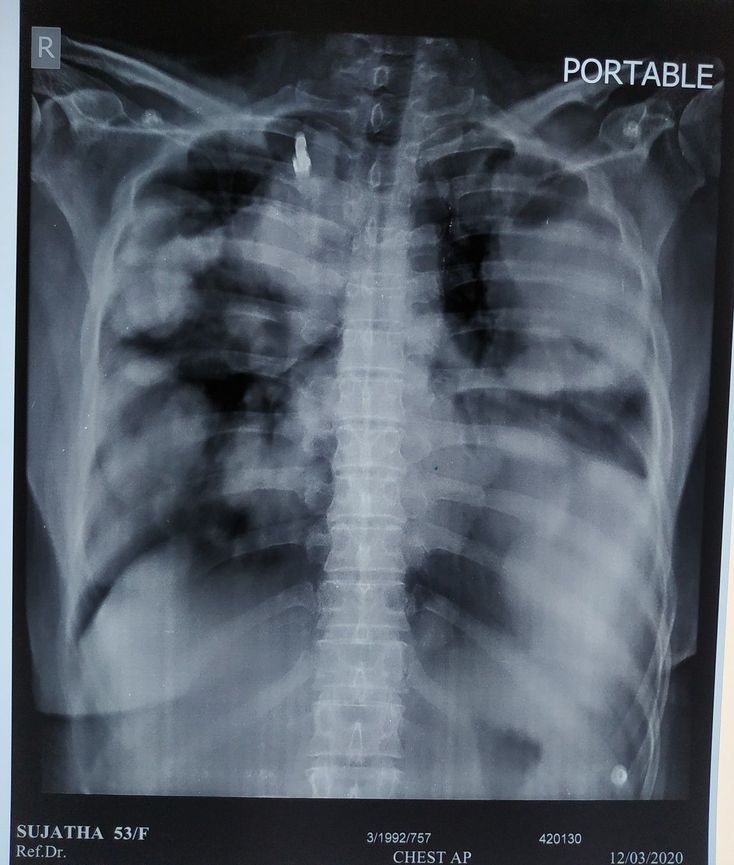

A 53 yr old female pt , k/c/o CA breast with lung metastasis detected 2 yrs back ,now presented with generelised weakness and decreased appetite for 2 days. h/o chest discomfort . No h/o fever, vomiting.No h/o DM,HTN .Her chest x-ray is mentioned above. Point out your findings and if possible pls suggest treatment plan .

Maybe pericardial effusion. All the lung field is consolidations due to metastasis.

Yeah . My professor told me that it is cannon ball appearance in the lung fields...